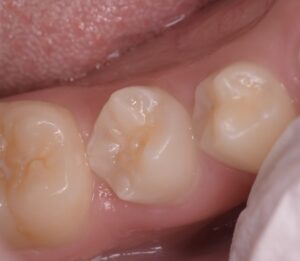

ここの真ん中の歯に中心結節があったが、そこの破折からの根管内への細菌感染とすぐに判断した。CBCTを撮影させていただき、歯根は完成しているため、再生歯内療法(REP)ではなく、MTAで根管充填をしようと計画

当日根管治療を実施し、根管充填まで行なった

翌日、痛みがないことを確認し、ダイレクトボンディングで治療を終了とした